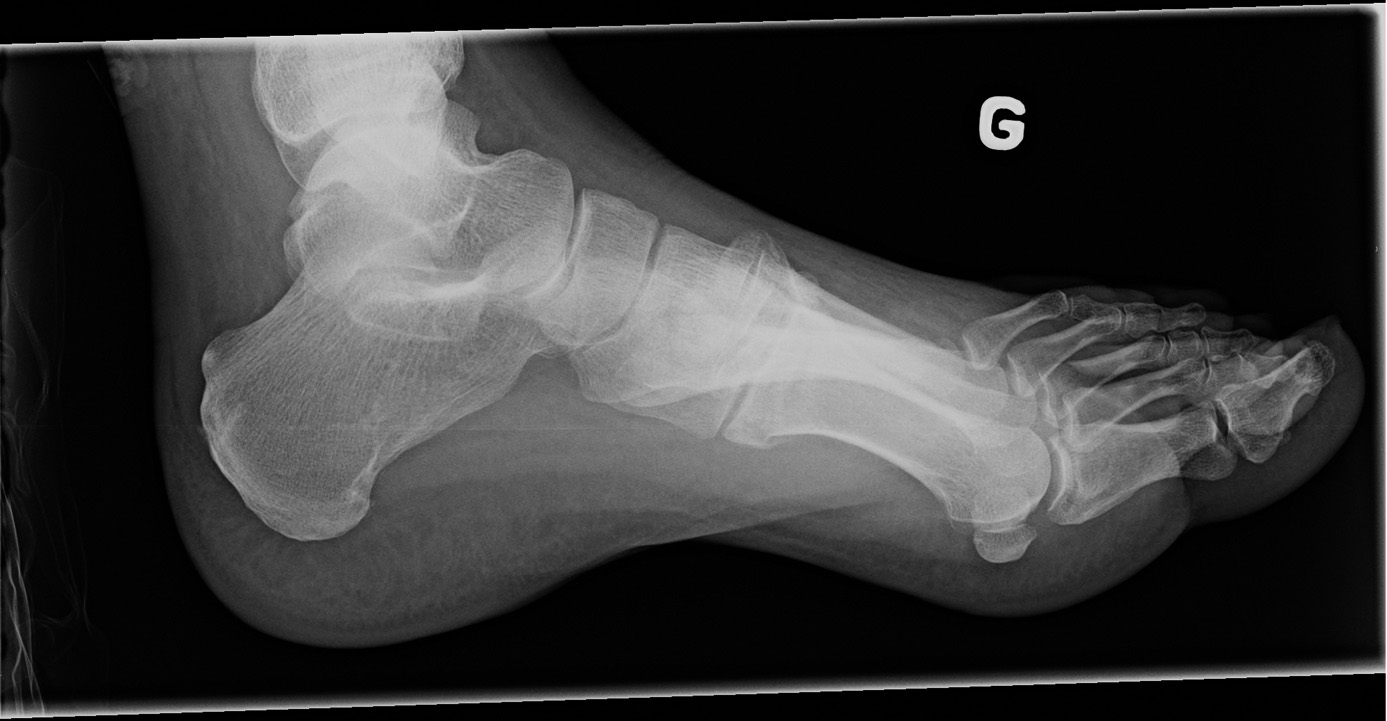

54-year-old male:

High velocity car crash.

Lisfranc fracture

First, note the base fractures of the 1st and 2nd metatarsal bones, minimally displaced, yet angulated in valgus. Second, note the three lateral metatarsal bones laterally displaced and with a varus angulation; the 3rd one is fractured and the 4th and 5th ones are dislocated. Thus, this is a Lisfranc fracture-dislocation of the divergent type. However, this is actually an atypical Lisfranc injury, for the 1st and 2nd metatarsals are both displaced medially and the 3rd, 4th and 5th are displaced laterally. In a classic Lisfranc injury, only the 1st metatarsal deviates medially, while the 2nd, 3rd, 4th and 5th are all displaced laterally.

Lateral